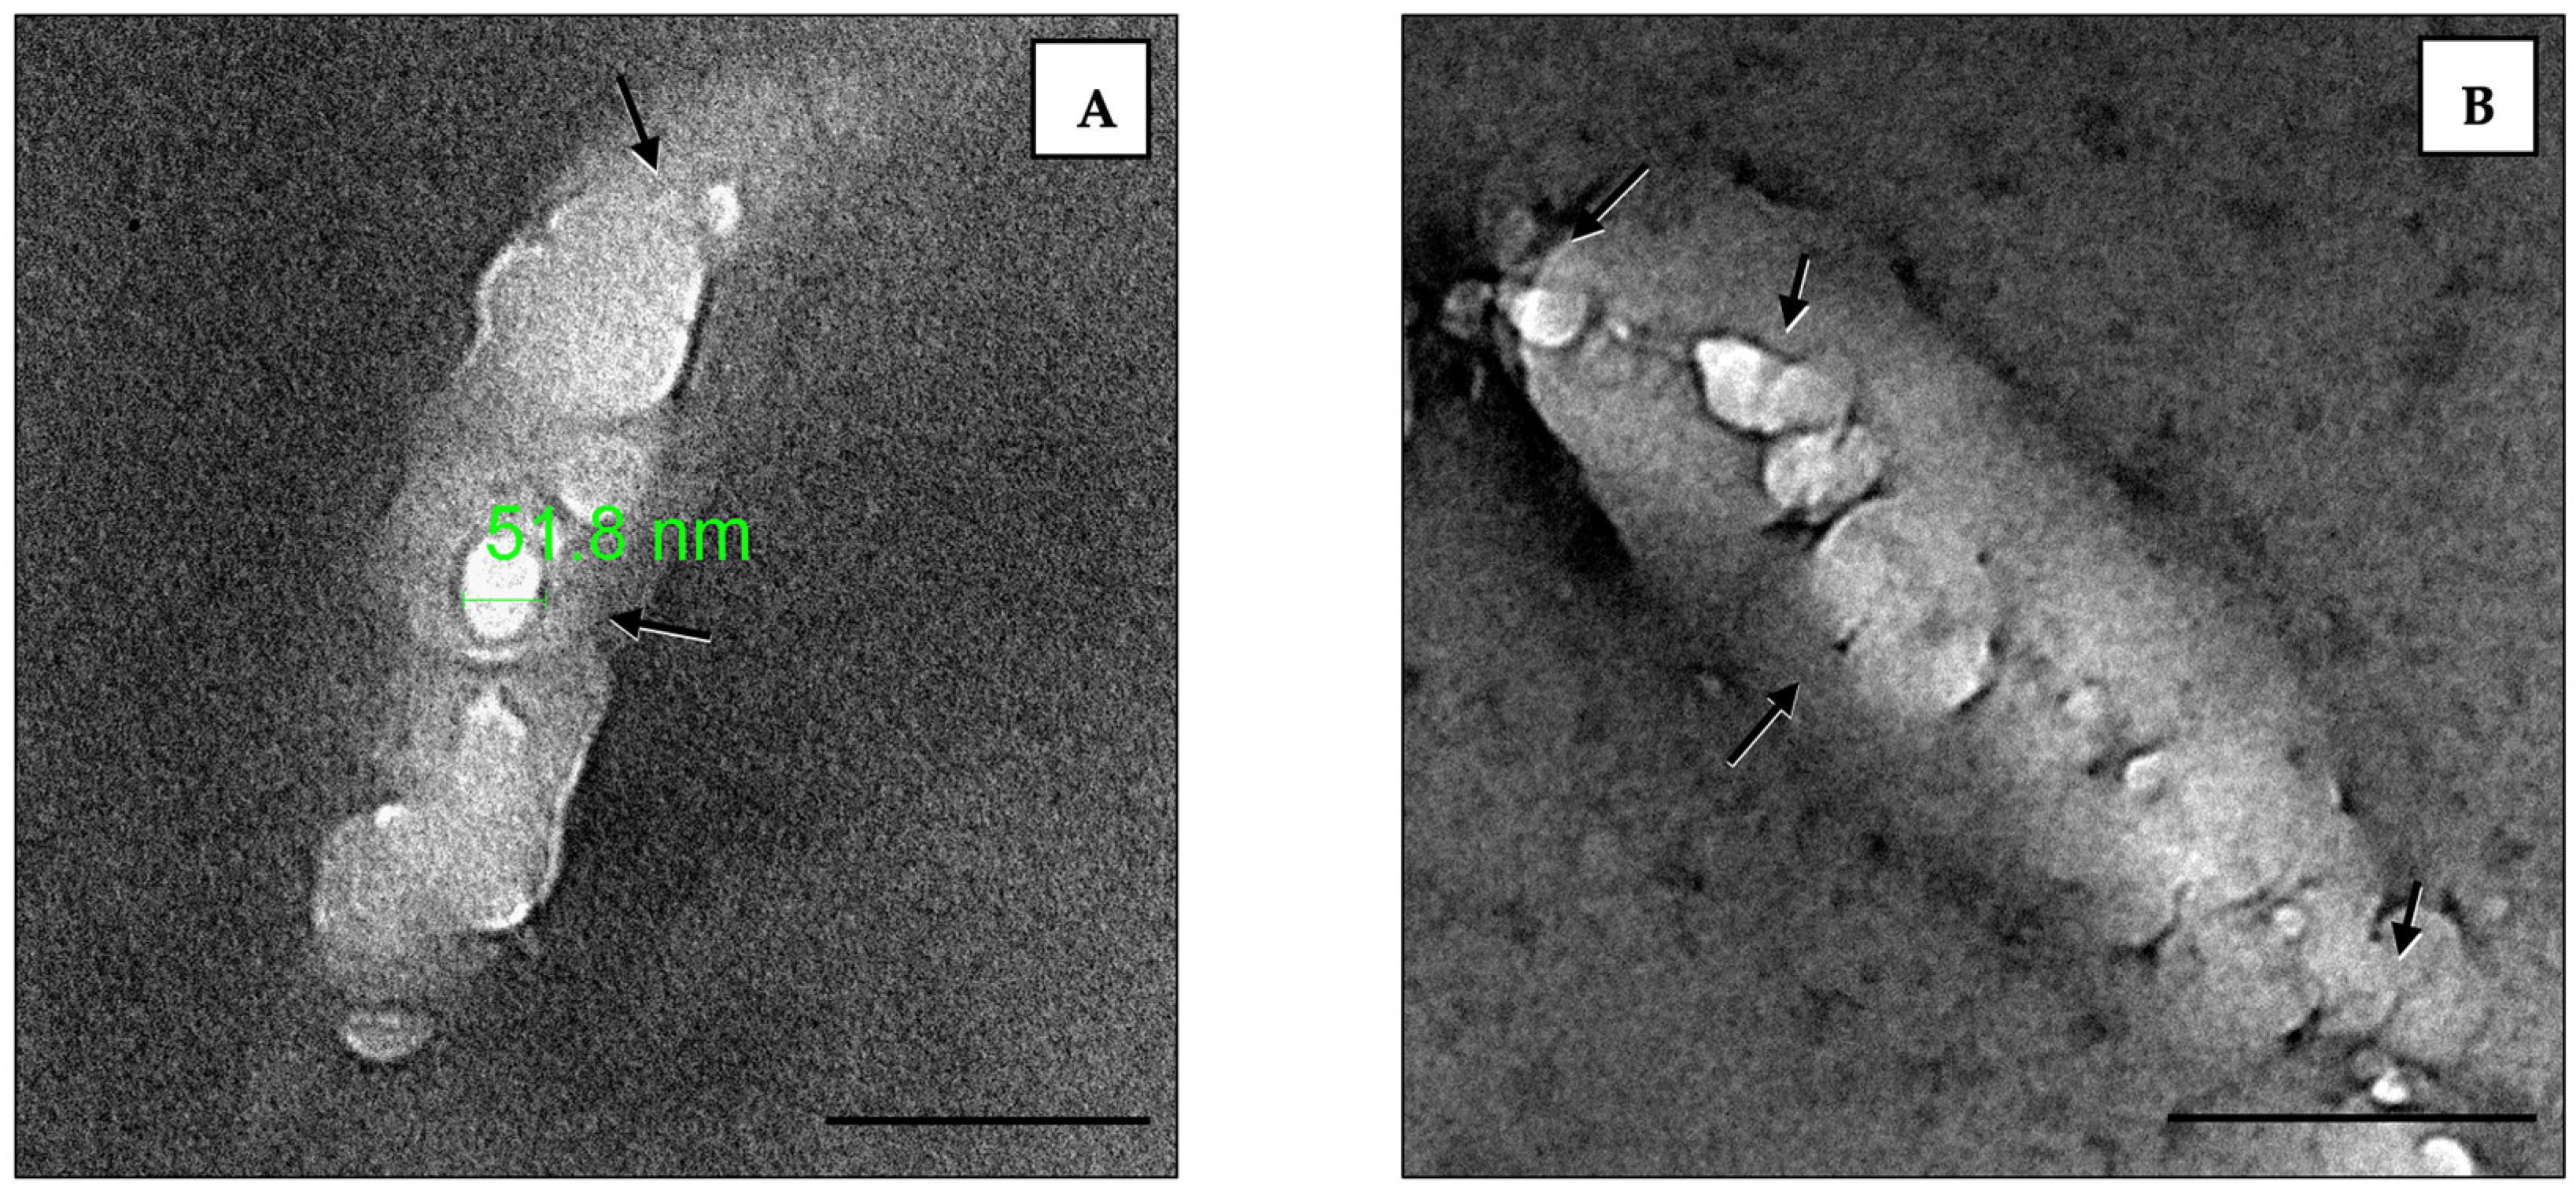

3.5. TEM Imaging of Loaded Liposomes (Lipo-GEN-THQ) Effect on Bacterial Ultrastructure